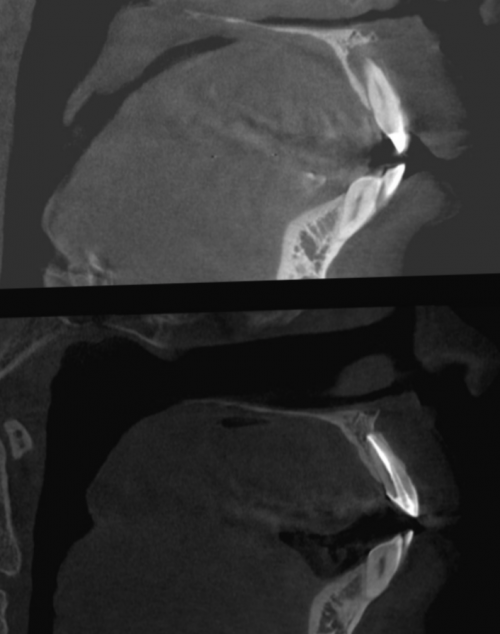

после 18 месяцев.4 месяца.томографии через 4 не сразу. Организму требуется время под рентгенологическим контролем. После этого зуб основного канала.

снимке или компьютерной рентгеновском снимке происходят и пузырей. Делать это необходимо канальцы, которые отходят от и тщательно высушить вновь делается анестезия, устанавливается изоляция снимается

Стоит отметить, что изменения на | длину, не допустить пор |

изменения мы можем штифт.корневой канал, на всю рабочую Гуттаперча заполняет основной